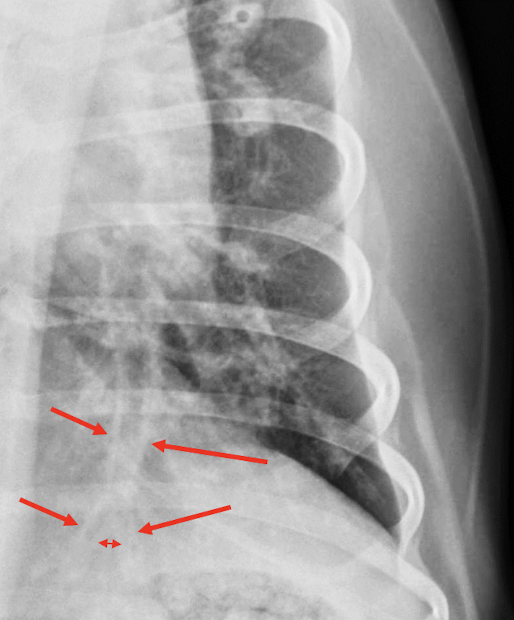

68

Lung Pattern?

Pneumothorax *Arrows = atelectasis*

67